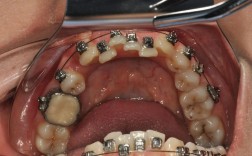

技术层面,主任需全面掌握各类矫治技术,包括传统金属托槽矫治、陶瓷托槽矫治、自锁托槽矫治、隐形矫治(如Invisalign、时代天使等)以及功能性矫治(如FRⅢ、Twin Block等),尤其擅长处理复杂病例,如骨性错颌畸形(III类骨面型、开颌等)、唇腭裂术后正畸、成人严重牙周病联合正畸治疗等,随着数字化正畸的普及,主任还需熟练运用口内扫描(如iTero、3Shape)、CBCT影像分析、计算机辅助设计(CAD)及3D打印等技术,实现精准诊断与个性化方案设计。